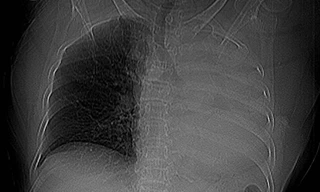

Sặc một viên thuốc, cụ bà xẹp toàn bộ phổi trái

TPO - Tối 18/1, Bệnh viện Đa khoa khu vực Quảng Nam (thành phố Đà Nẵng) cho hay đã tiếp nhận một bệnh nhân nhập viện trong tình trạng ho nhiều đột ngột kèm khó thở sau khi uống thuốc.